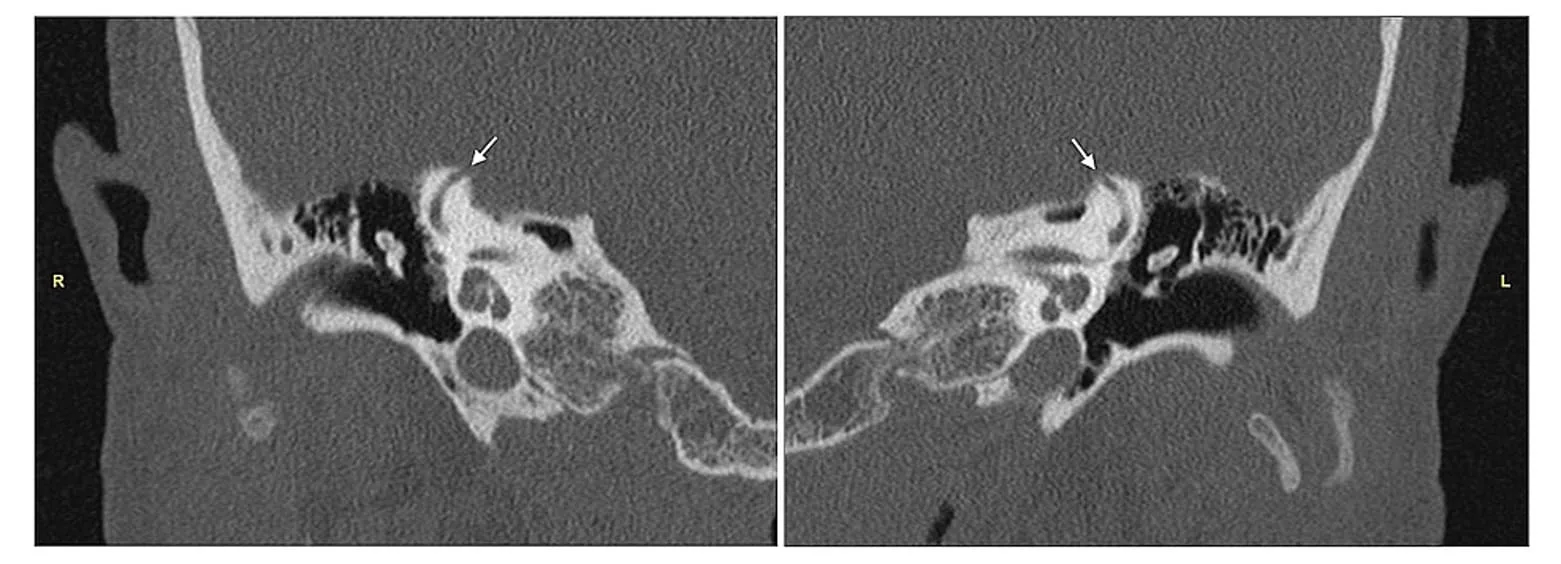

Superior Semisirküler Kanal Dehissansı (SSCD), iç kulaktaki superior semisirküler kanalın üst kısmındaki kemiğin incelmesi veya açık hale gelmesi ile karakterize bir durumdur.

SSCD, iç kulakta bulunan superior semisirküler kanalın üzerinde normalde olması gereken kemik tabakasının incelmesi veya bir açıklık oluşması durumudur. Bu durum, işitme ve denge sistemlerini etkileyebilir.